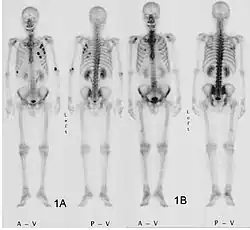

- Vues de fractures pathologiques

Fracture pathologique de l'humérus sur une métastase de carcinome du rein

Fracture pathologique du bras gauche sur une métastase osseuse de cancer du sein

Scintigraphie corps entier avec 99mTc-HDP de la patiente avec une fracture du bras due à une métastase du cancer du sein